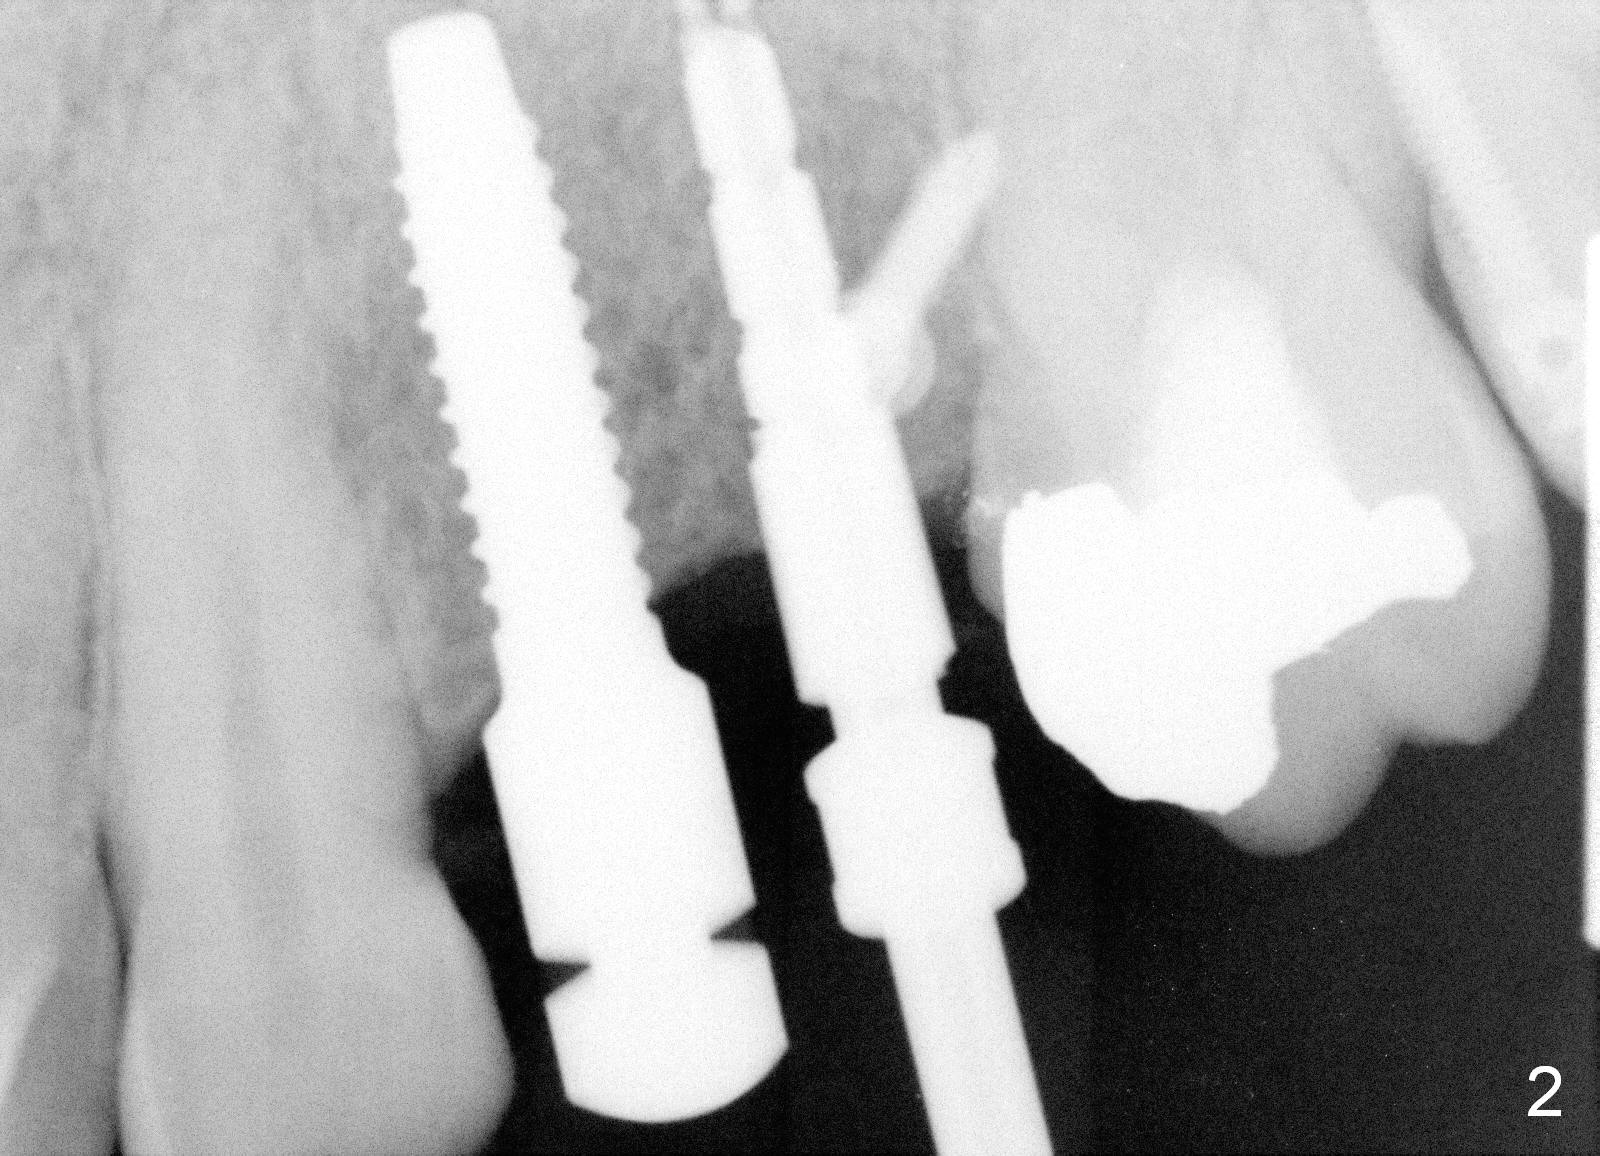

A 51-year-old man returns for #12,13 implant placement 2 years post extraction (Fig.1, 2 mm pilot drills 11 mm deep). Bone expanders are used (Fig.2 E), although the bone density is high. Two of 4x17 mm implant are placed with insertion torque > 60 Ncm (Fig.3). Four months postop, the implants are prepared for provisional as anchorage for limited ortho (Fig.4). When intrusion of #14 is finished, permanent crowns are fabricated for #12 and 13. Fig.5 is taken 1 year 1 months post cementation.